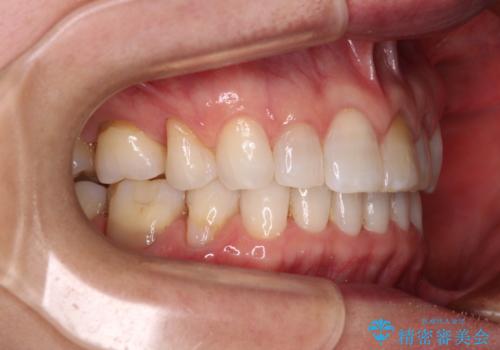

矯正治療の後戻り インビザライン・ライトでの再矯正

- 上下前歯を中心に、以前行った矯正治療の後戻りが気になるとのことで来院された患者様です。

後戻りは軽度であったため、インビザライン・ライトにて治療を行うこととしました。

矯正治療後は、再度後戻りすることを極力回避するために、下顎前歯の舌側を細いワイヤーを用いて保定することとしました。